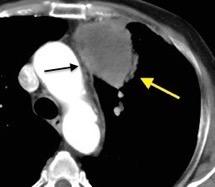

Diafragma “colgante” (“dangling sign”)

(“Dangling sign”)

TC. Mejor con multicorte. (reconstrucciones).

Asociación: Aire en pared.

Fracturas costal .Rotura esplénica. Neumoperitoneo.

Diafragma discontinúo Herniación de la grasa omental

Desser TS et al.The dangling diaphragm sign: sensitivity and comparison with existing CT signs of blunt traumatic diaphragmatic rupture. Emerg Radiol 2010